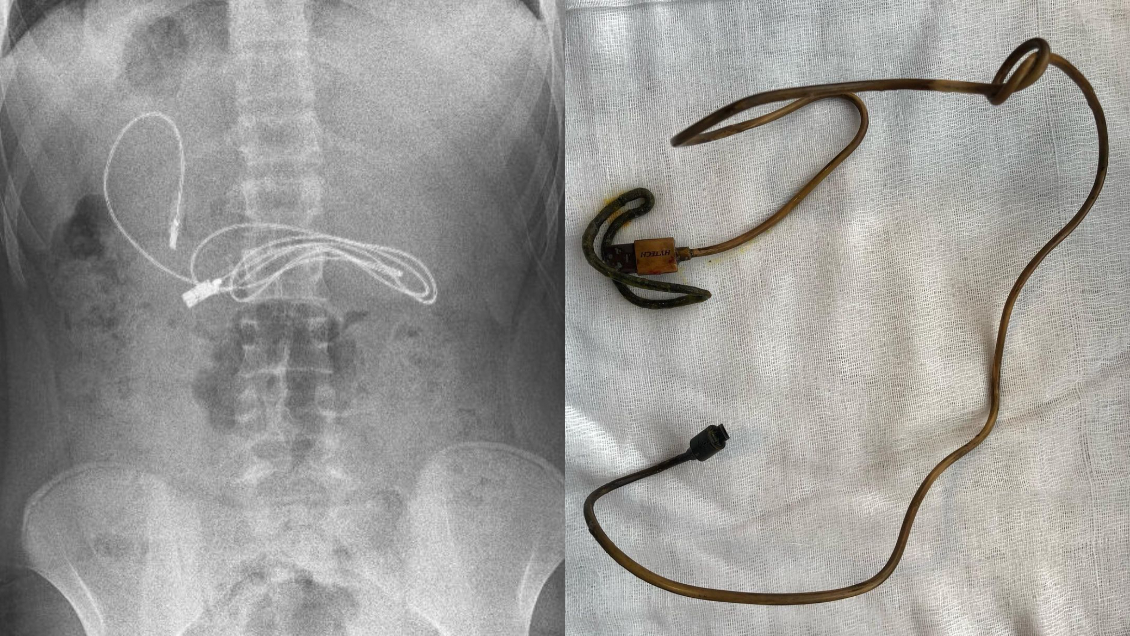

Médicos extrajeron cable USB de un metro de largo del estómago de un adolescente

"Tuvimos dificultades para quitar el cable, ya que un extremo había pasado al intestino delgado", comentó el médico a cargo de la cirugía.